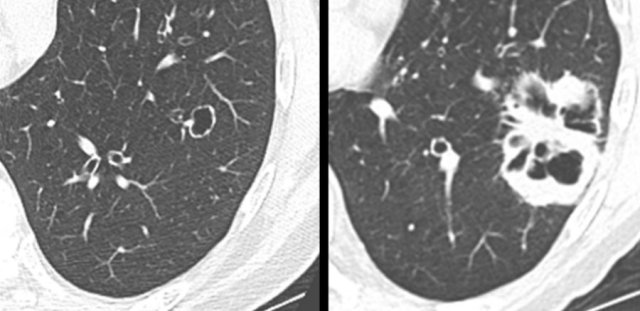

These images are of a patient with a left lower lobe cystic squamous cell carcinoma (left panel), who developed a right lower lobe cystic lesion (right panel) and subcarinal lymphadenopathy 3 years into follow-up.

Although initially considered contralateral metastatic disease, recommended tissue analysis showed an unrelated second primary squamous cell carcinoma on histopathology.